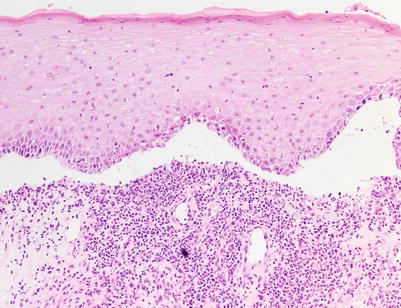

Fig. 5.4

Interface dermatitis (lichenoid type) with subepidermal clefting, corresponding to aGVHD histologic grade III (H&E, 100× magnification)